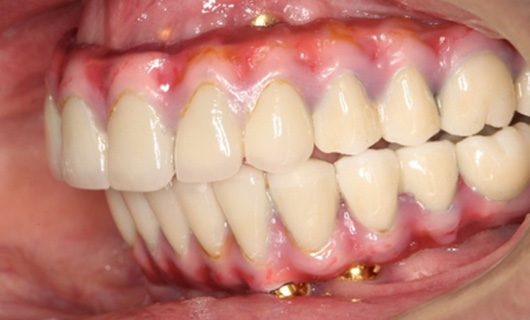

Dentures that are supported by an implant can provide significant improvements in chewing and smiling. In contrast to regular complete dentures, these dentures are horseshoe-shaped reducing bulkiness and creating more space on the palate for better tasting ability. A person with implant-supported dentures can enjoy fruits, vegetables, steaks, corn on the cob, and other foods compared to a person wearing traditional dentures. In addition, implant-support dentures significantly boost patients’ confidence to smile and speak.

Implant supported dentures can be fixed or semi-fixed. Fixed dentures are not removable and will be removed only by a dentist during regular dental check-ups. The semi-fixed dentures are removable and can be cleaned, maintained the same way as regular dentures.

- Fabrication of final denture: Once you and your dentist have decided on a final fit and appearance, a dental technician or prosthodontist will construct a final prosthesis that is durable and natural-looking.

- They function like normal teeth

- These dentures are sturdy and do not need any adhesive